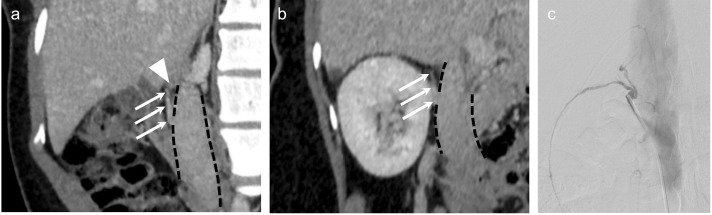

肾上腺静脉采样(AVS)失败通常是由于难以采样右肾上腺静脉(RAV)。正常情况下,小房室是尾侧定向的,然而,小房室的颅侧定向并不罕见。在这种情况下,使用多用途(MPA)导管形状可能有助于采样。2014年至2019年期间,351例患者接受了AVS和RAV采样,其中23例患者(7%,10M:13F)。收集AVS前成像、手术细节和AVS结果的数据,以IVC右侧壁为颅侧轴(0°定义为尾侧,180°定义为颅侧),在静脉造影中测量RAV垂直角度,并评估使用MPA导管成功取样前使用导管数量与各种手术措施的相关性。23例患者均在术中静脉造影时进行了颅面导向的AVS,技术上成功进行了24例AVS。在2例已知的颅向RAVs患者中,首选MPA导管。在其余患者中,21% (n= 5)的患者选择MPA导管作为第二选择,50% (n= 12)的患者选择MPA导管作为第三选择,最多的患者选择MPA导管作为第八选择(n=1)。早期使用MPA导管与较短的透视时间(R = 0.71, P = 0.0001)和较低的造影剂(R = 0.77, P < 0.0001)相关。这些结果支持MPA导管在颅向RAVs取样时的使用。当颅向RAV存在时,当尾向导管不能识别RAV时,应考虑使用MPA导管。

Adrenal vein sampling (AVS) failure is often attributed to difficulty sampling the right adrenal vein (RAV). Normally, the RAV is caudally oriented, however, cranial orientation of the RAV is not uncommon. In such cases, use of a multipurpose (MPA) catheter shape may facilitate sampling. Between 2014 and 2019, 351 patients underwent AVS and RAV sampling with an MPA catheter occurred in 23 patients (7%, 10M:13F). Data regarding pre-AVS imaging, procedural details, and AVS results were collected, the RAV vertical angle was measured on venography using the IVC right lateral wall as the craniocaudal axis (0° defined as caudal, 180° cranial), and correlation of the number of catheters used until successful sampling with the MPA catheter and various procedural measures was assessed. Twenty-four technically successfully AVS were performed in 23 patients, all of whom had cranially oriented RAVs on intra-procedural venography. An MPA catheter was the first choice in 2 patients with previously known cranially oriented RAVs. In the remaining patients, the MPA catheter was 2nd choice in 21% (n = 5), 3rd choice in 50% (n = 12), and up to 8th choice (n=1). Early utilization of the MPA catheter correlated with lower fluoroscopic time (R = 0.71, P = 0.0001) and lower contrast volume (R = 0.77, P < 0.0001). These results support the use of the MPA catheter when sampling cranially oriented RAVs. MPA catheters should be readily considered when cranially oriented RAVs are present and when caudally-oriented catheters fail to identify the RAV.